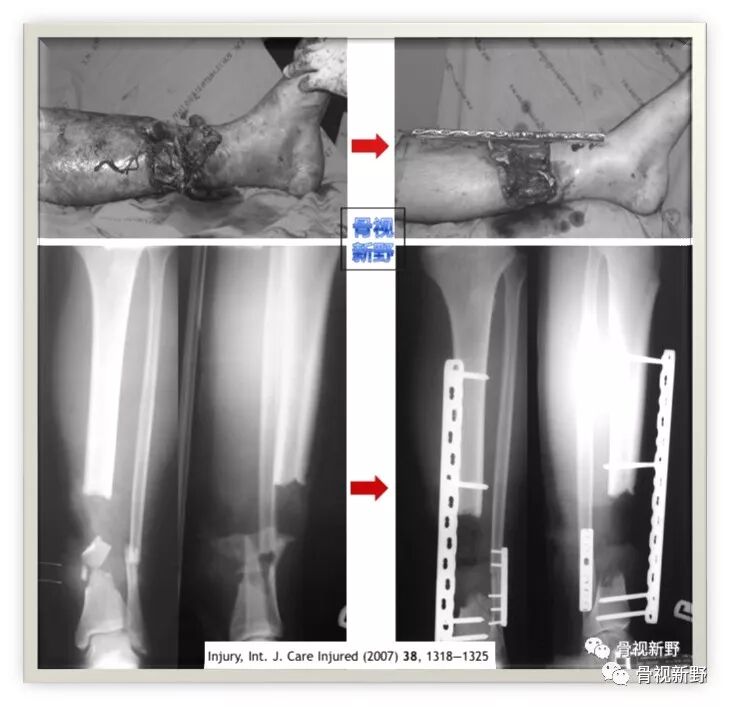

(T.Apivatthakakul,2007年)

2007年,泰国医生T.Apivatthakakul等人年首次报道了将锁定加压钢板(locking compression plate,LCP)用于胫骨开放性骨折并骨缺损的外固定治疗1例,取得了较好的固定效果。

锁定钢板的外固定应用

Case

29岁,男。车祸致左胫腓骨开放骨折,皮肤软组织缺损面积9cm×15cm ,并胫骨节段性骨缺损。急诊清创、胫骨以14孔4.5mm锁定加压钢板(LCP)作外固定(钢板距离皮肤4cm间距)。

● 1周后,皮肤软组织缺损以游离股前外侧肌皮瓣修复。

● 4周后,皮瓣愈合,开始作骨搬移(截骨第7天开始搬运、前3周每天0.5mm;1 mm/天);期间作主、被动关节活动及部分负重。

● 96天后,搬移骨段到达骨端,自体髂骨植骨促进愈合。

● 5个月后,拆除Wagner牵引外架;骨段通过LCP打入1枚螺钉进行稳定。

LCP继续外固定5月(外固定共10月)后拆除LCP;骨折愈合,踝关节功能良好。